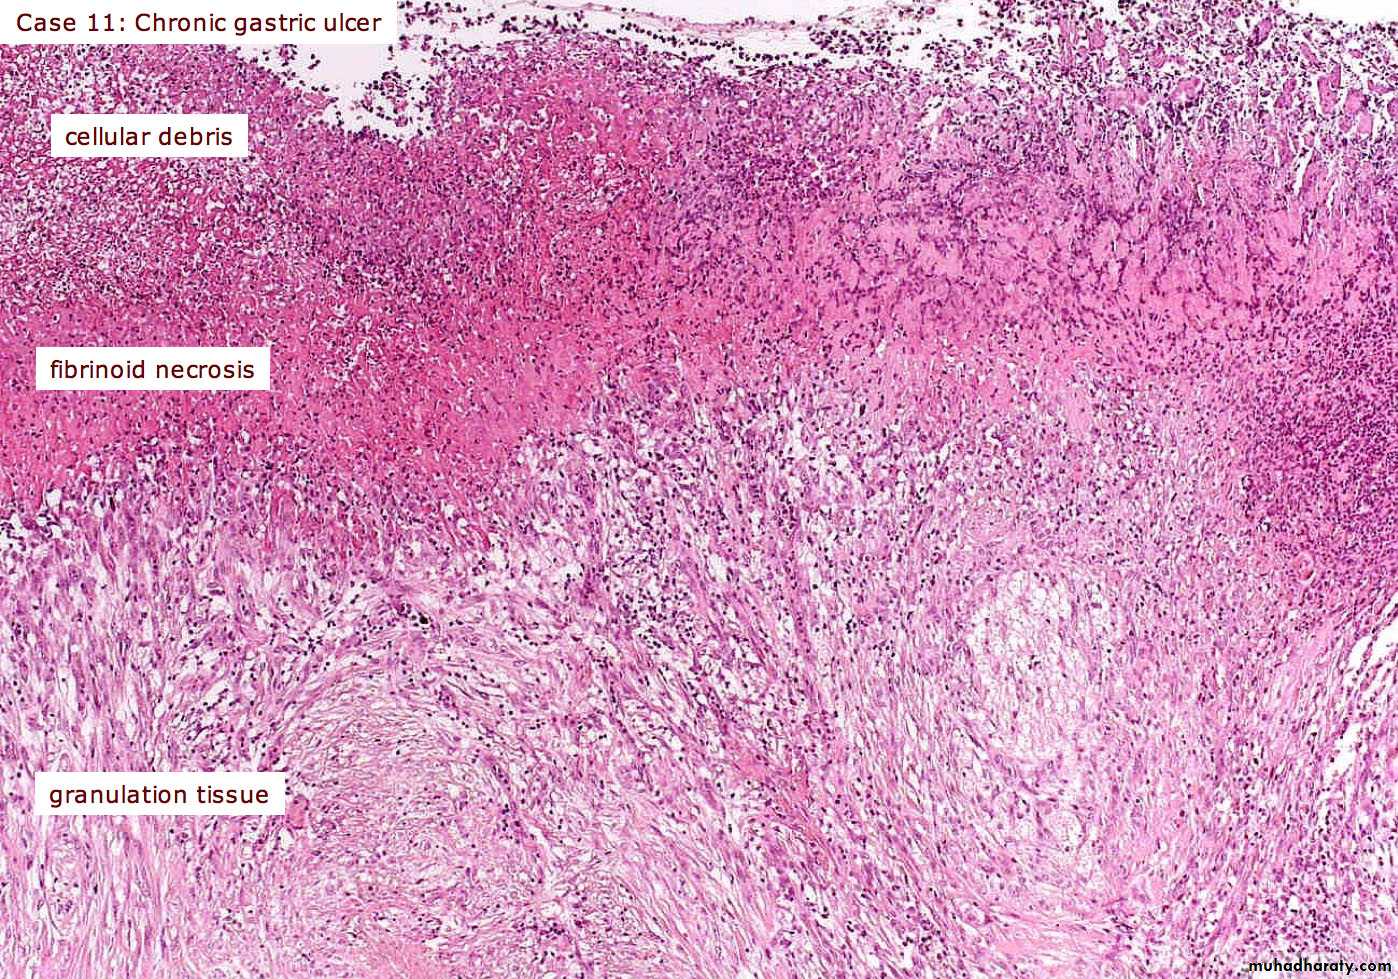

granulation t